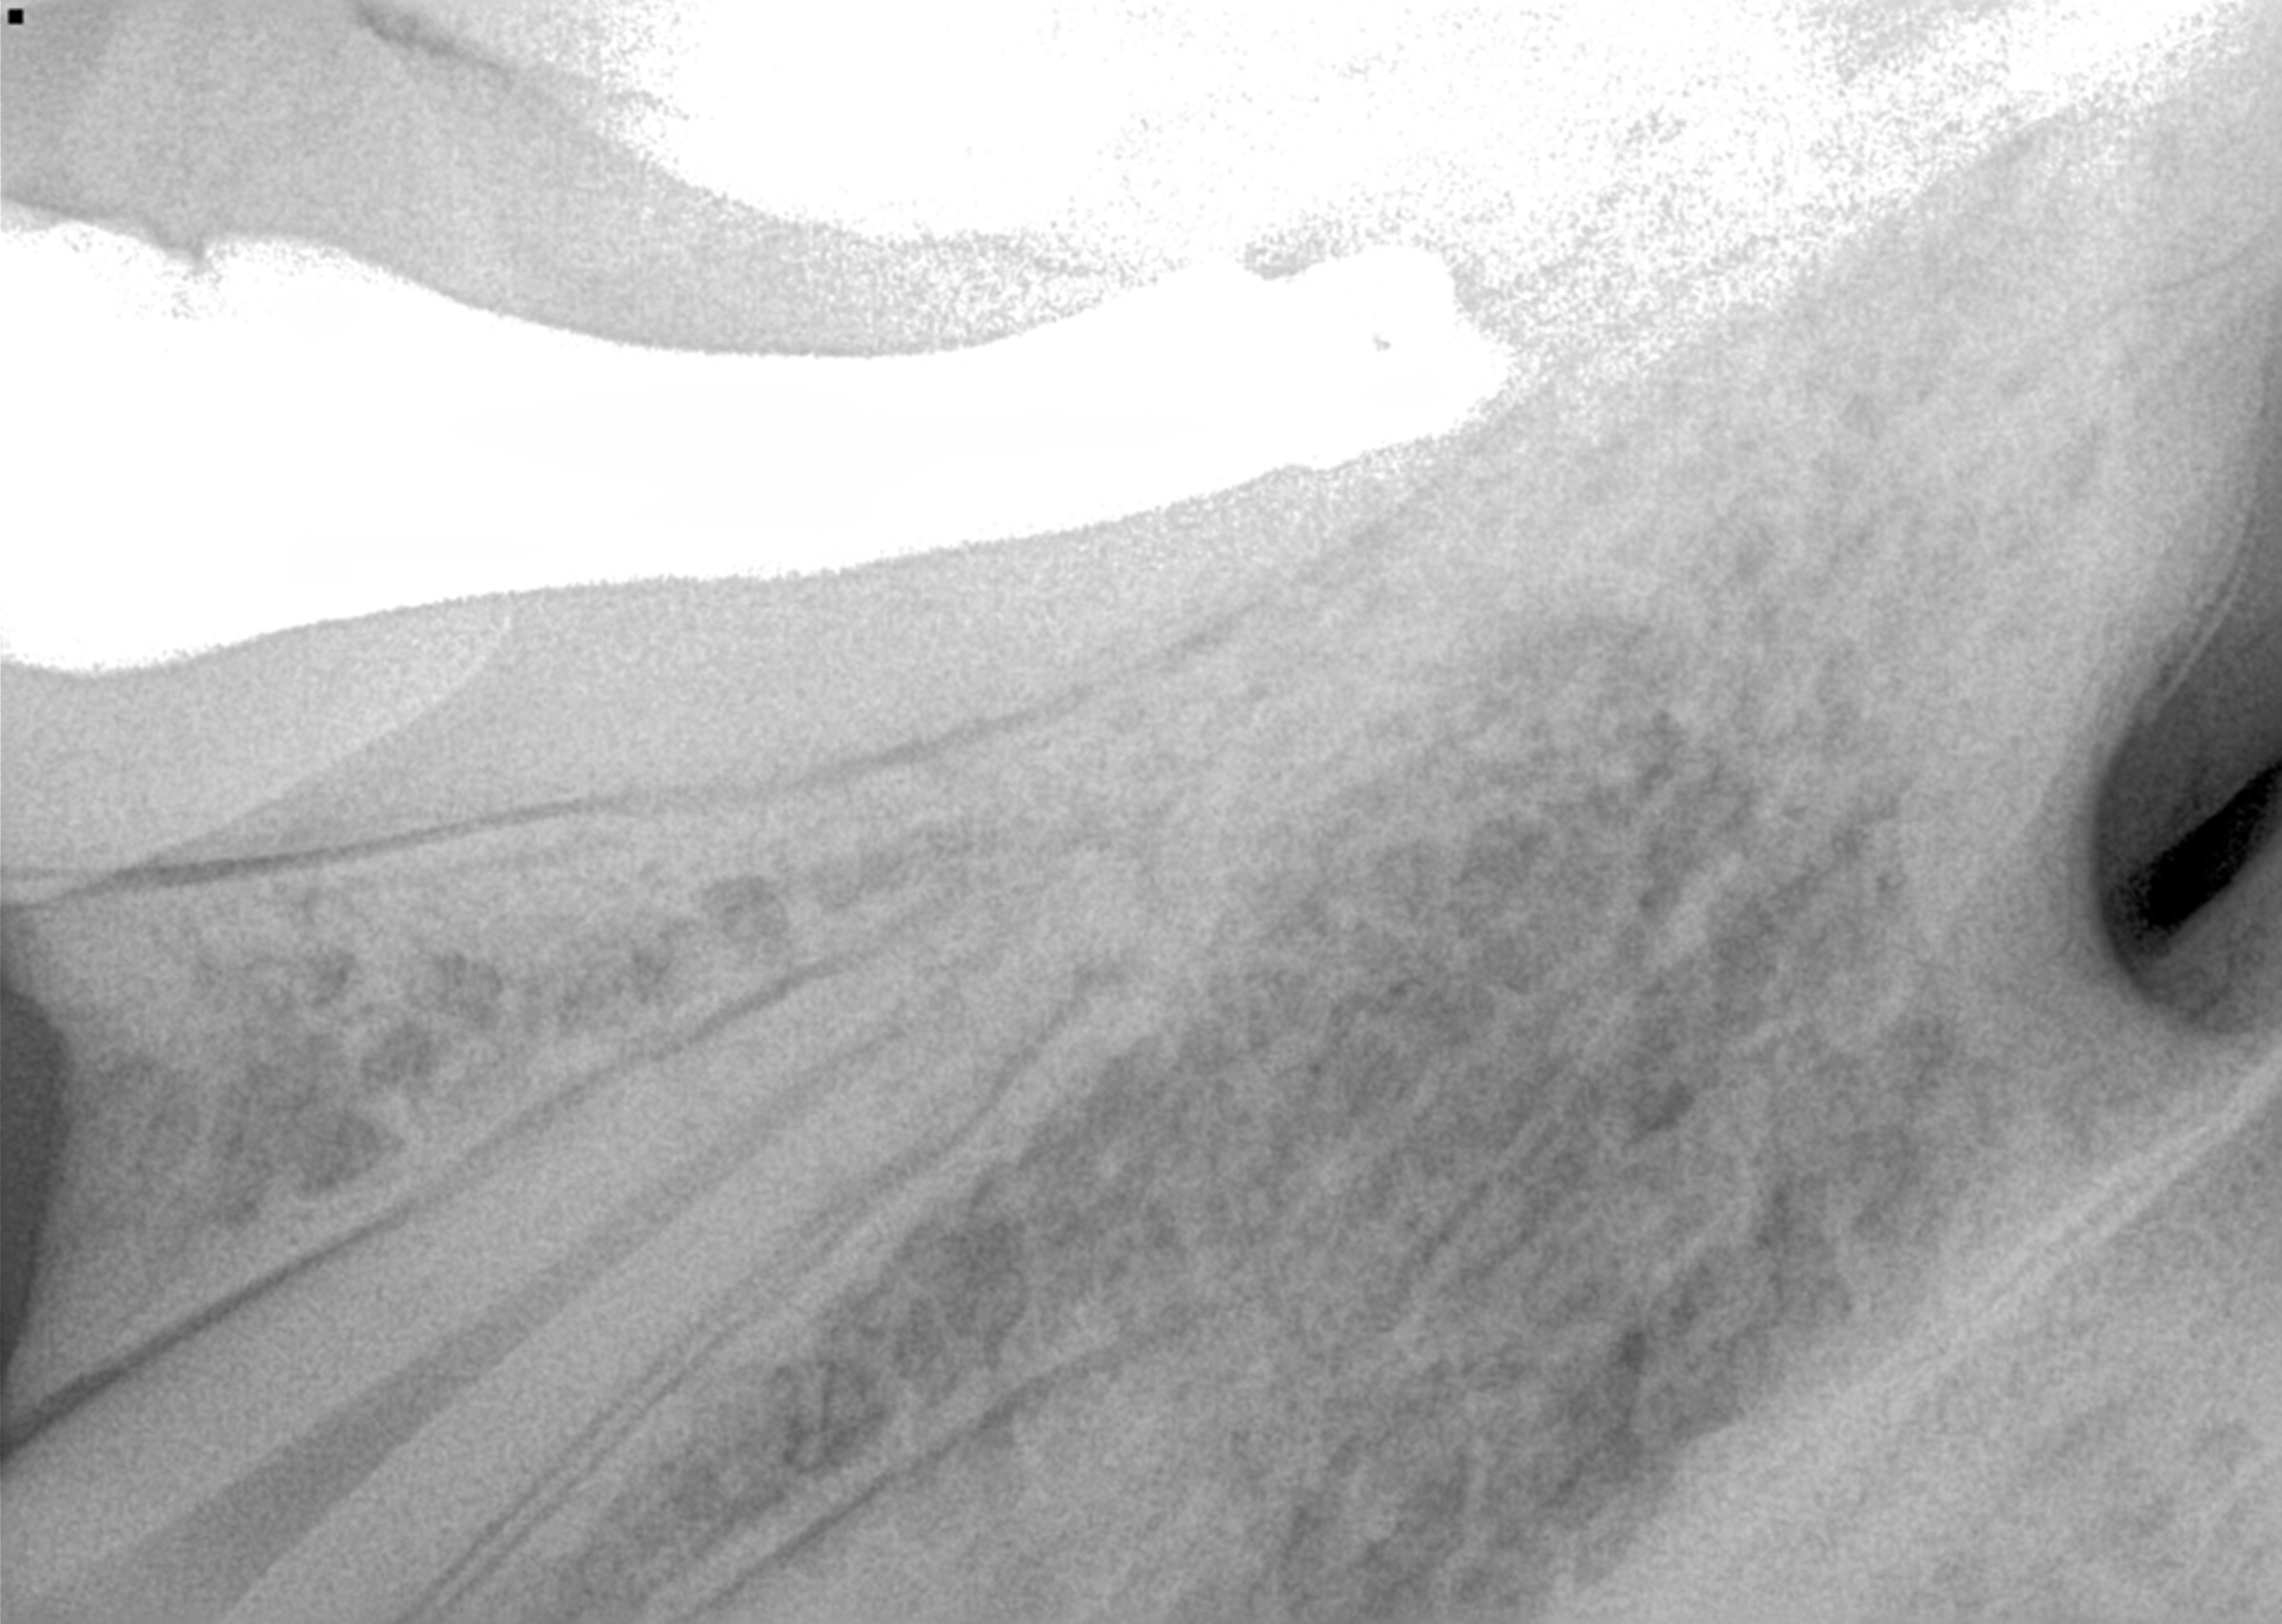

Digital image reveals periapical lesion on central incisor residual root.